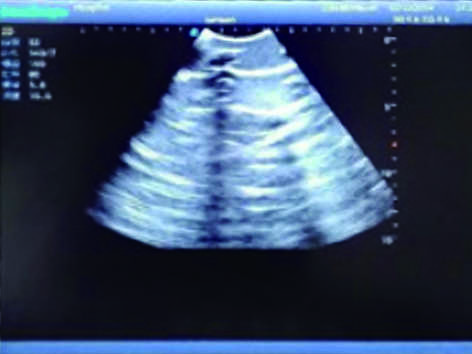

Pneumothorax & Thoracic Closed Drainage Ultrasound Training Model

Model TYE1566

2)  Made of high molecular polymer ultrasound material, close to the real skin. It can conduct ultrasound-guided puncture exercises with various clinical models of real ultrasound machines.

3)  Showing clear and real images of the tissues and organs (including muscle and connective tissue, air-containing lung tissue, pleural structure)